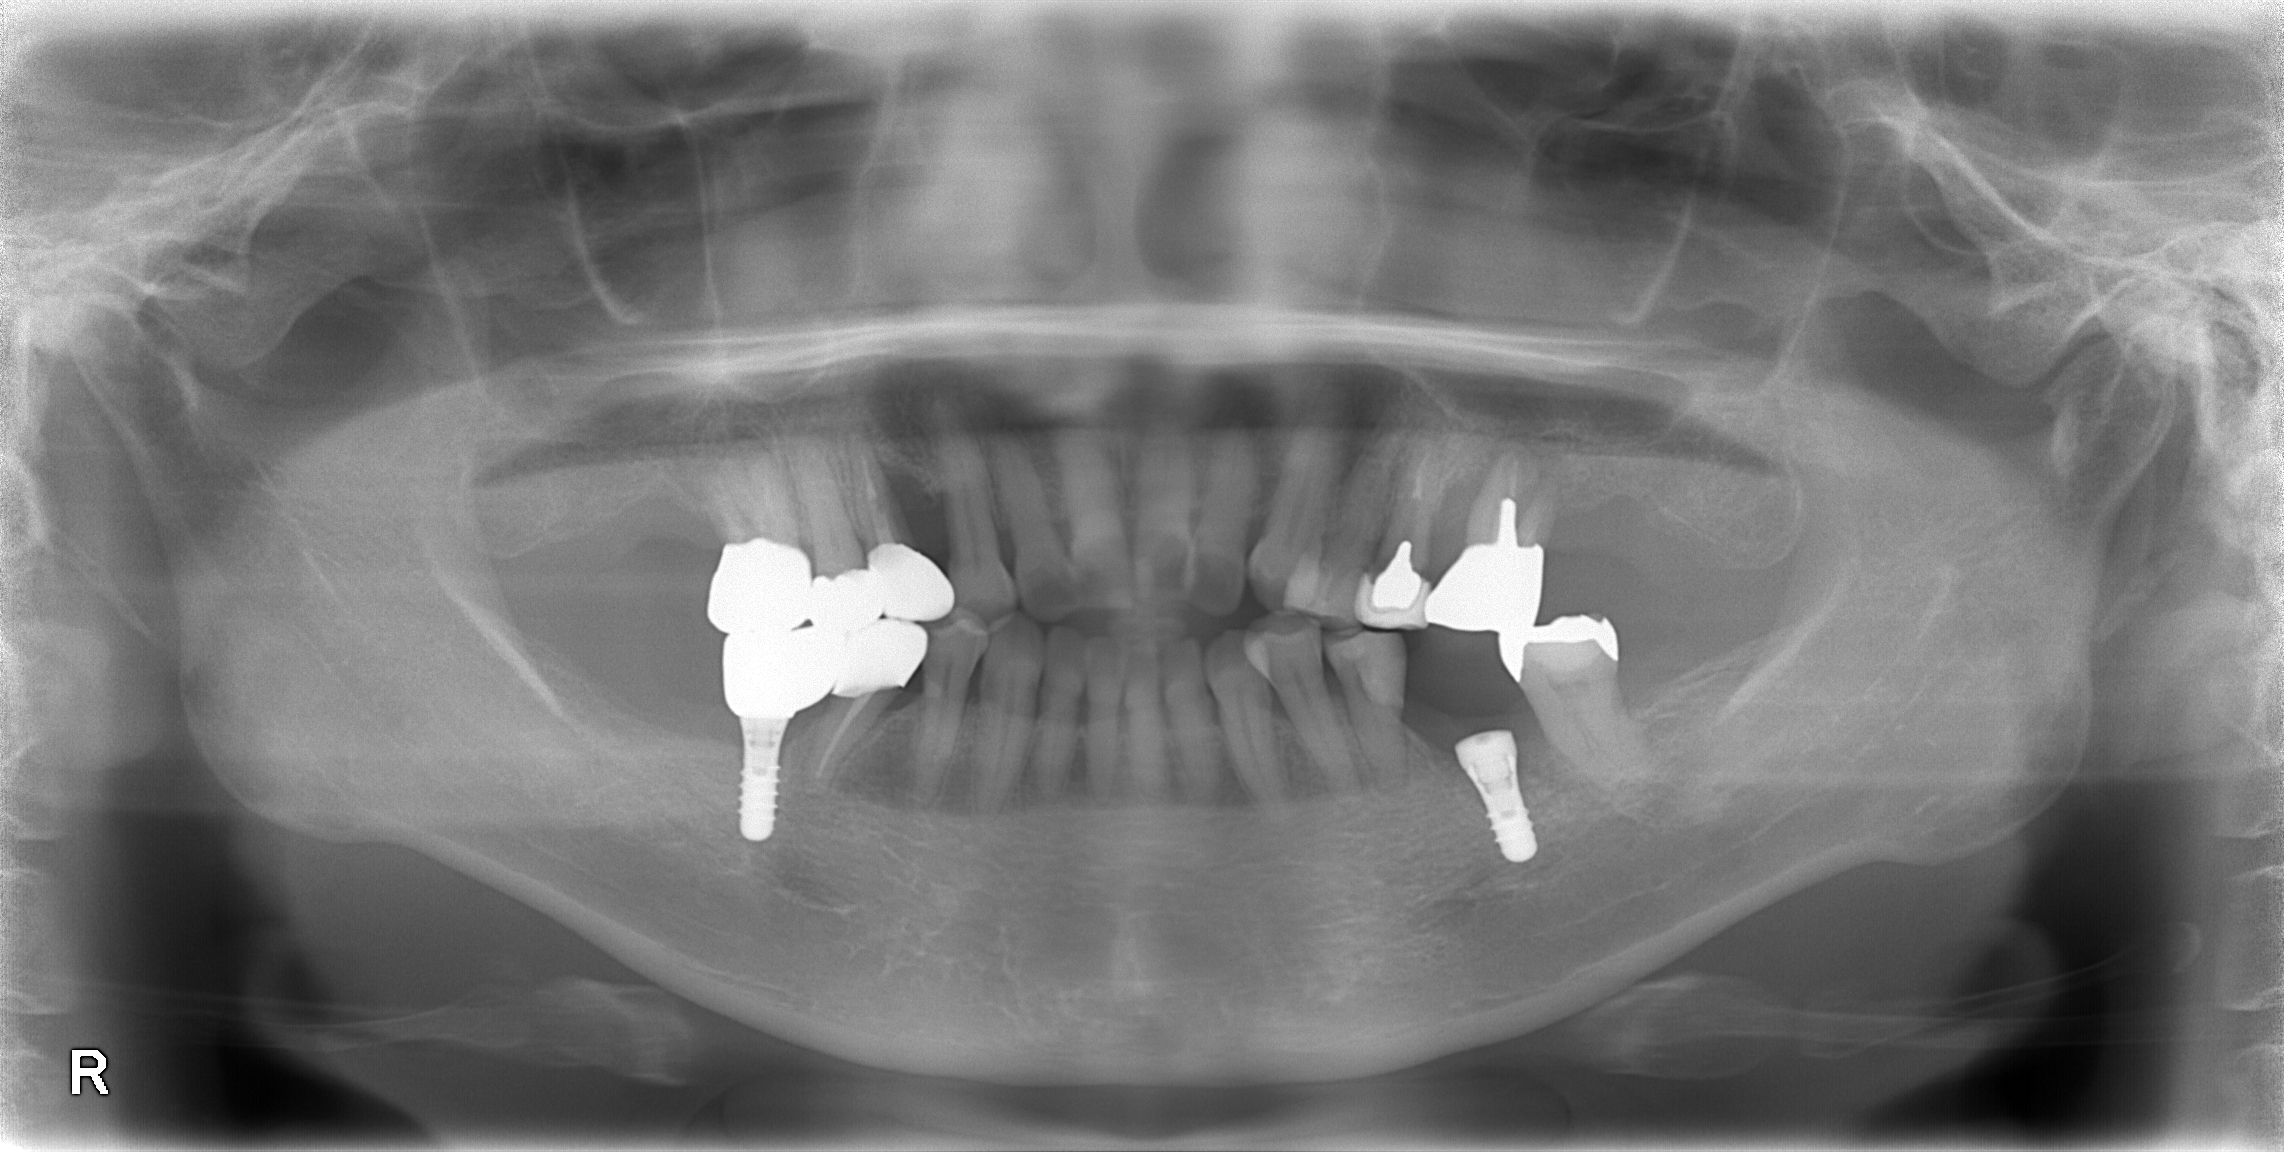

重度虫歯からのインプラント・入れ歯治療(*^-^*)